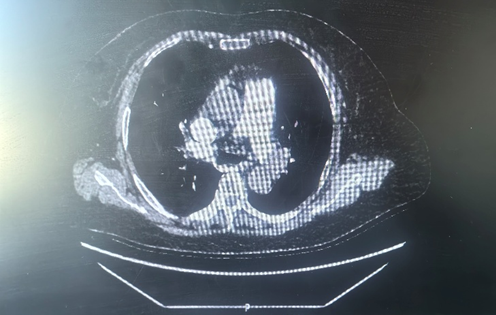

术前CT

,D-⼆聚体 2230 ng/mL,BNP 1288pg/L,肌钙蛋白I 0.18ng/mL ,双下肢血管彩超提示“双侧下肢浅静脉迂曲增宽并血栓形成”,心脏彩超提示“右心及左房扩大、肺动脉高压(轻度)、EF:33%”,肺动脉增强 CT 提示“双侧肺动脉主干及其分支多发栓塞”,明确诊断为“ 急性肺栓塞” 。